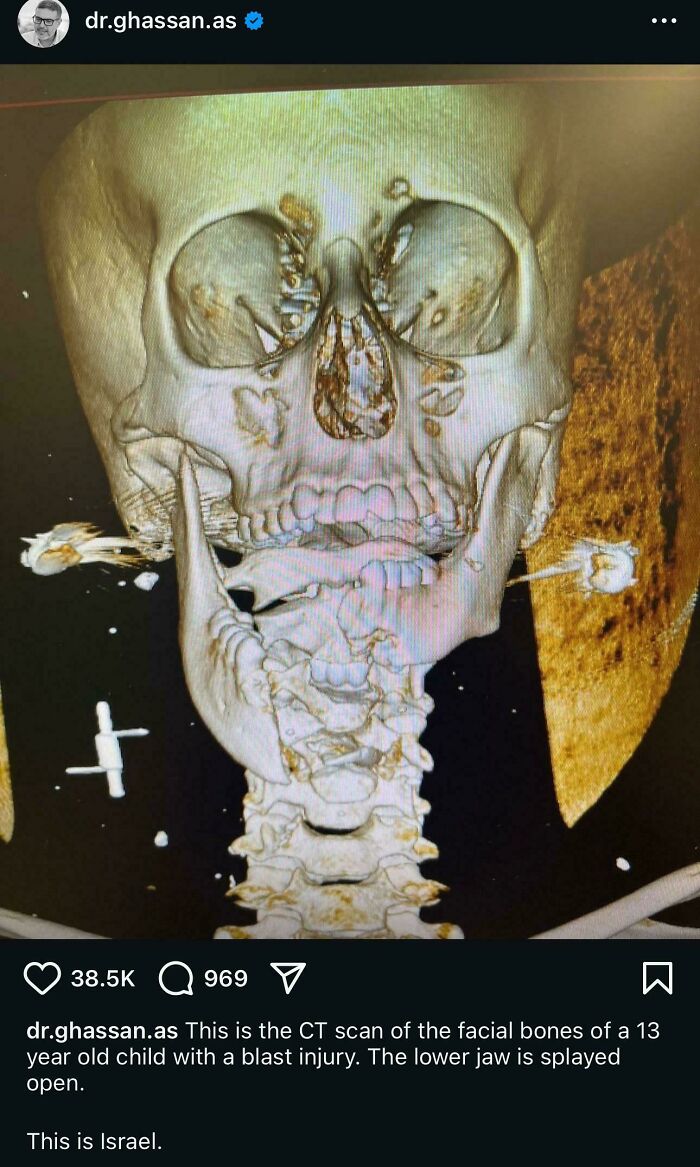

#20 CT Scan Of A 13 Year Old From Gaza

Image credits: AssadShal